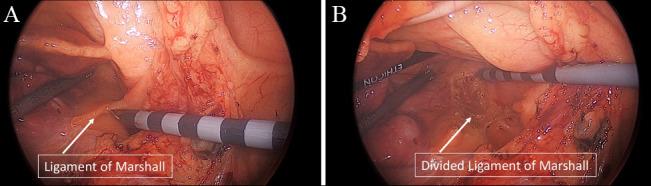

非阵发性心房颤动的杂交消融:汇聚式和完全胸腔镜入路

非阵发性心房颤动持续困扰着电生理学家和外科医生。单纯的心内膜导管消融术效果不尽人意,尽管体外循环下的Cox迷宫手术效果极佳,但因其侵入性,在转诊机构和外科医生中都未得到广泛应用。CONVERGE IDE试验为这个曾经模糊不清的问题带来了新的曙光。电生理学家和外科医生现在正通过混合团队消融方法共同努力,提供一种联合消融策略,改善了患者预后,并重新点燃了为改善患者预后所需的合作。我们在此总结目前用于非阵发性心房颤动的混合团队消融方法(CONVERGE和完全胸腔镜手术)。